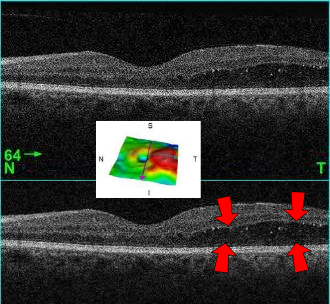

DME (당뇨황반부종)

진단: OCT에서 황반부 망막 두께 증가(중심와 두께, CST 증가) 또는 안저검사에서 황반부 부종/경성삼출물이 확인될 때 진단합니다. NPDR/PDR 어느 단계에서든 동반 가능하며, 당뇨망막병증에서 시력저하의 가장 흔한 원인입니다.

- Center-involving DME (CI-DME): 중심와(fovea) 침범 — 시력에 직접 영향, anti-VEGF 치료 대상

CI-DME는 시력 예후에 결정적이므로, OCT에서 **중심와 두께(CST)**를 반드시 확인하세요. CST > 300μm이면 일반적으로 치료 대상입니다.

- OCT: DME 평가의 gold standard. CST, 망막내/하액 평가